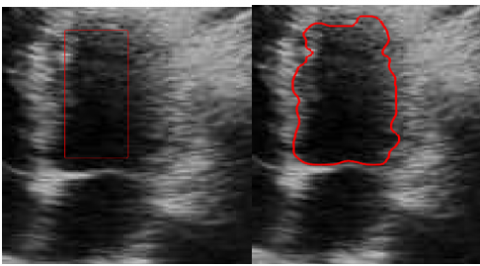

In Figure 11, we present the segmentation results applied to both MRI and ultrasound images, obtained using the DRLS (Distance Regularized Level Set) algorithm. The parameters used to segment MRI and ultrasound images were selected after several tests to achieve precise and rigorous segmentation that accurately defines the target contour.

(a) The cardiac ultrasound image

(b) The cardiac MRI image

(c) The ultrasound image

Figure 11. Segmentation results of MRI and echographic images

Using the parameters μ=0.04, λ=5, α=-1, σ=5 and 200 iterations, the segmentation of the cardiac ultrasound image demonstrates the effectiveness of the DRLSE algorithm in accurately detecting the edges of the cardiac wall, even in the presence of noise (Figure 11(a)). The moderate regularization ensured by μ=0.04 preserves the details of the contours, while λ=5 strikes a balance between contour attraction and stability. The parameter α=−1 enhances the algorithm’s ability to handle noisy regions, and σ=5 reduces noise while maintaining critical transitions in the image.

The set of parameters μ, λ, α, and σ allows for accurate and robust segmentation, proving the adaptability of the algorithm to the challenges posed by ultrasound images.

For the MRI heart image, the segmentation with the parameters μ=0.2, λ=1, α=1, σ=6, and 200 iterations demonstrates the DRLSE algorithm's ability to effectively highlight contrasts between different tissues, allowing for precise localization of the targeted contour (Figure 11(b)).

For the image shown in Figure 11(c), segmentation with the parameters μ =0.2, λ =5, α =-1, σ =6, and 200 iterations produces a satisfactory result. The segmented contours are both sufficiently sharp and well defined, while maintaining a certain smoothness that prevents the influence of noise. These parameter values provide an optimal compromise between fidelity to the image intensity data and contour smoothness, resulting in accurate segmentation while minimizing imperfections due to artifacts or noise.